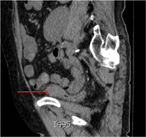

Neuroendocrine carcinoma as a rare cause of jejunal intussusception in an adult. Management and literature review

Georgios Sahsamanis and others

Journal of Surgical Case Reports, Volume 2017, Issue 5, May 2017, rjx082, https://doi.org/10.1093/jscr/rjx082